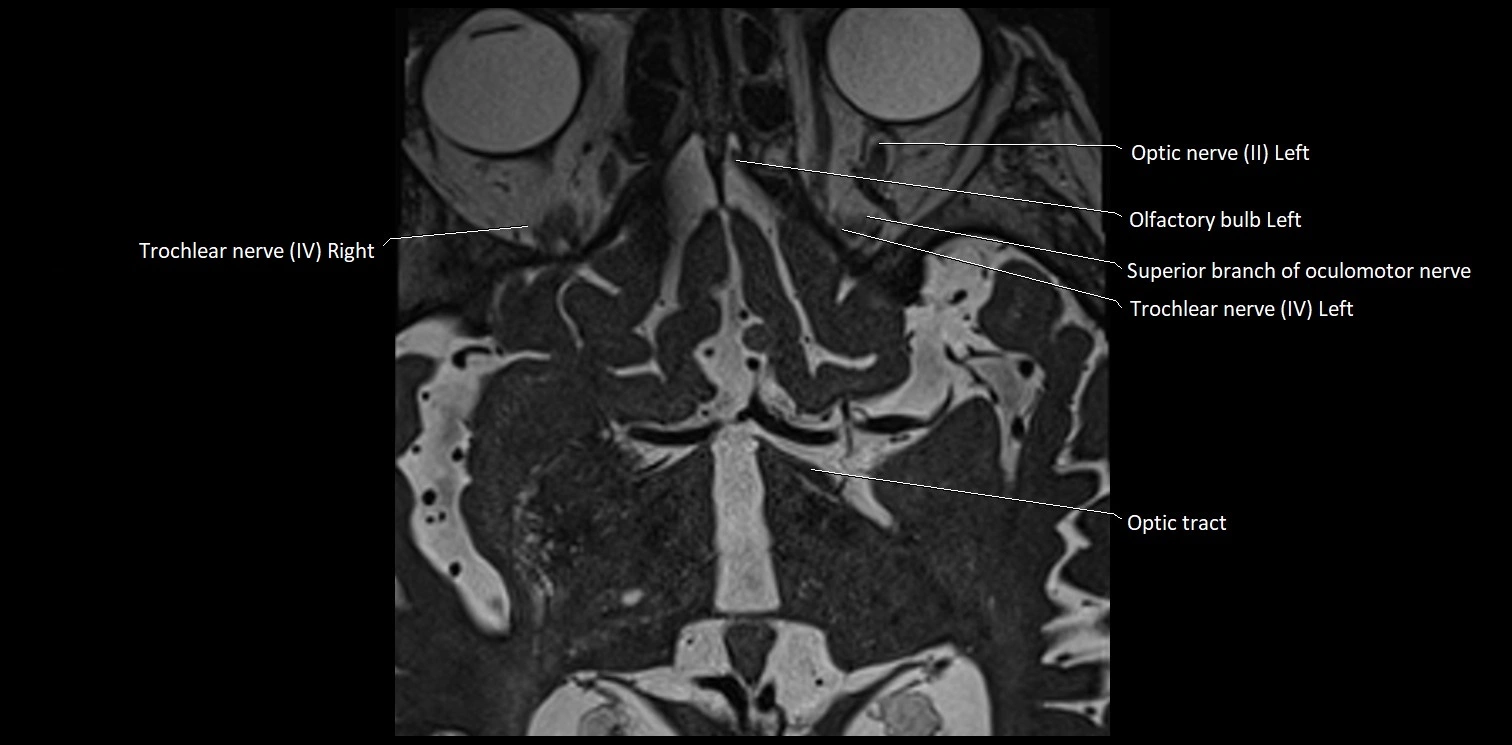

MRI Appearance

• The abducens nerve is a small, thin, linear structure

• Best visualized on high-resolution T2-weighted 3D MRI sequences (e.g., FIESTA or CISS)

• Seen as a hypointense (dark) line running from the brainstem at the pontomedullary junction, traversing the prepontine cistern, and entering Dorello’s canal under the petrosphenoidal ligament, then into the cavernous sinus, and finally the orbit

• May be challenging to visualize in standard MRI due to its small size

• Pathology may be inferred by absence, displacement, or enhancement of the nerve

MRI images

image